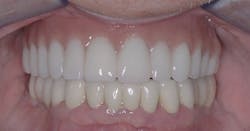

Unlike a removable prosthesis, a fixed prosthesis can seldom be constructed to fully replace the contours of the face that were present before the teeth were extracted (figure 2). Why is that so? The pink soft-tissue replacement material—currently mostly polymethyl methacrylate or zirconia—must be reduced in contour and opened up enough to allow for cleaning of the prosthesis. The prosthesis cannot have a ridge lap (saddle) design, as with a removable design. The apical portion of the prosthesis must be convex because the convex design allows the underside of the prosthesis to be cleaned with pipe cleaners, a Waterpik water flosser (Water Pik Inc.), floss, or other oral hygiene aids. The flanges of the prosthesis usually cannot be contoured to the optimum degree allowed by a removable prosthesis, which can be taken out of the mouth for cleaning.

Due to all the reasons explained above, the esthetic result can almost always be better with a removable prosthesis.